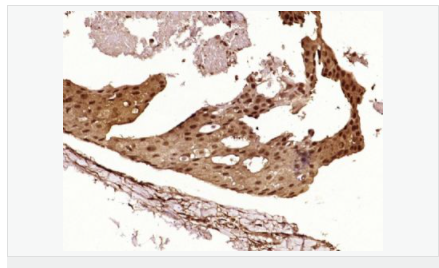

| 產品應用 | WB=1:500-2000 ELISA=1:5000-10000 IHC-P=1:100-500 IHC-F=1:100-500 Flow-Cyt=1μg/Test ICC=1:100 IF=1:100-500 (石蠟切片需做抗原修復) not yet tested in other applications. optimal dilutions/concentrations should be determined by the end user. |

| 產品介紹 | This gene encodes a tumor suppressor protein containing transcriptional activation, DNA binding, and oligomerization domains. The encoded protein responds to diverse cellular stresses to regulate expression of target genes, thereby inducing cell cycle arrest, apoptosis, senescence, DNA repair, or changes in metabolism. Mutations in this gene are associated with a variety of human cancers, including hereditary cancers such as Li-Fraumeni syndrome. Alternative splicing of this gene and the use of alternate promoters result in multiple transcript variants and isoforms. Additional isoforms have also been shown to result from the use of alternate translation initiation codons (PMIDs: 12032546, 20937277). [provided by RefSeq, Feb 2013]. Function: Acts as a tumor suppressor in many tumor types; induces growth arrest or apoptosis depending on the physiological circumstances and cell type. Involved in cell cycle regulation as a trans-activator that acts to negatively regulate cell division by controlling a set of genes required for this process. One of the activated genes is an inhibitor of cyclin-dependent kinases. Apoptosis induction seems to be mediated either by stimulation of BAX and FAS antigen expression, or by repression of Bcl-2 expression. Implicated in Notch signaling cross-over. Prevents CDK7 kinase activity when associated to CAK complex in response to DNA damage, thus stopping cell cycle progression. Isoform 2 enhances the transactivation activity of isoform 1 from some but not all TP53-inducible promoters. Isoform 4 suppresses transactivation activity and impairs growth suppression mediated by isoform 1. Isoform 7 inhibits isoform 1-mediated apoptosis. Subunit: Interacts with AXIN1. Probably part of a complex consisting of TP53, HIPK2 and AXIN1 (By similarity). Binds DNA as a homotetramer. Interacts with histone acetyltransferases EP300 and methyltransferases HRMT1L2 and CARM1, and recruits them to promoters. In vitro, the interaction of TP53 with cancer-associated/HPV (E6) viral proteins leads to ubiquitination and degradation of TP53 giving a possible model for cell growth regulation. This complex formation requires an additional factor, E6-AP, which stably associates with TP53 in the presence of E6. Interacts (via C-terminus) with TAF1; when TAF1 is part of the TFIID complex. Interacts with ING4; this interaction may be indirect. Found in a complex with CABLES1 and TP73. Interacts with HIPK1, HIPK2, and TP53INP1. Interacts with WWOX. May interact with HCV core protein. Interacts with USP7 and SYVN1. Interacts with HSP90AB1. Interacts with CHD8; leading to recruit histone H1 and prevent transactivation activity (By similarity). Interacts with ARMC10, BANP, CDKN2AIP, NUAK1, STK11/LKB1, UHRF2 and E4F1. Interacts with YWHAZ; the interaction enhances TP53 transcriptional activity. Phosphorylation of YWHAZ on 'Ser-58' inhibits this interaction. Interacts (via DNA-binding domain) with MAML1 (via N-terminus). Interacts with MKRN1. Interacts with PML (via C-terminus). Interacts with MDM2; leading to ubiquitination and proteasomal degradation of TP53. Directly interacts with FBXO42; leading to ubiquitination and degradation of TP53. Interacts (phosphorylated at Ser-15 by ATM) with the phosphatase PP2A-PPP2R5C holoenzyme; regulates stress-induced TP53-dependent inhibition of cell proliferation. Interacts with PPP2R2A. Interacts with AURKA, DAXX, BRD7 and TRIM24. Interacts (when monomethylated at Lys-382) with L3MBTL1. Isoform 1 interacts with isoform 2 and with isoform 4. Interacts with GRK5. Binds to the CAK complex (CDK7, cyclin H and MAT1) in response to DNA damage. Interacts with CDK5 in neurons. Interacts with AURKB, UHRF2 and NOC2L. Interacts (via N-terminus) with PTK2/FAK1; this promotes ubiquitination by MDM2. Interacts with PTK2B/PYK2; this promotes ubiquitination by MDM2. Interacts with PRKCG. Interacts with human cytomegalovirus/HHV-5 protein UL123. Subcellular Location: Cytoplasm. Nucleus. Nucleus, PML body. Endoplasmic reticulum. Note=Interaction with BANP promotes nuclear localization. Recruited into PML bodies together with CHEK2. Isoform 1: Nucleus. Cytoplasm. Note=Predominantly nuclear but localizes to the cytoplasm when expressed with isoform 4. Isoform 2: Nucleus. Cytoplasm. Note=Localized mainly in the nucleus with minor staining in the cytoplasm. Isoform 3: Nucleus. Cytoplasm. Note=Localized in the nucleus in most cells but found in the cytoplasm in some cells. Isoform 4: Nucleus. Cytoplasm. Note=Predominantly nuclear but translocates to the cytoplasm following cell stress. Isoform 7: Nucleus. Cytoplasm. Note=Localized mainly in the nucleus with minor staining in the cytoplasm. Isoform 8: Nucleus. Cytoplasm. Note=Localized in both nucleus and cytoplasm in most cells. In some cells, forms foci in the nucleus that are different from nucleoli. Isoform 9: Cytoplasm. Tissue Specificity: Ubiquitous. Isoforms are expressed in a wide range of normal tissues but in a tissue-dependent manner. Isoform 2 is expressed in most normal tissues but is not detected in brain, lung, prostate, muscle, fetal brain, spinal cord and fetal liver. Isoform 3 is expressed in most normal tissues but is not detected in lung, spleen, testis, fetal brain, spinal cord and fetal liver. Isoform 7 is expressed in most normal tissues but is not detected in prostate, uterus, skeletal muscle and breast. Isoform 8 is detected only in colon, bone marrow, testis, fetal brain and intestine. Isoform 9 is expressed in most normal tissues but is not detected in brain, heart, lung, fetal liver, salivary gland, breast or intestine. Post-translational modifications: Acetylated. Acetylation of Lys-382 by CREBBP enhances transcriptional activity. Deacetylation of Lys-382 by SIRT1 impairs its ability to induce proapoptotic program and modulate cell senescence. Phosphorylation on Ser residues mediates transcriptional activation. Phosphorylated by HIPK1. Phosphorylation at Ser-9 by HIPK4 increases repression activity on BIRC5 promoter. Phosphorylated on Thr-18 by VRK1. Phosphorylated on Ser-20 by CHEK2 in response to DNA damage, which prevents ubiquitination by MDM2. Phosphorylated on Ser-20 by PLK3 in response to reactive oxygen species (ROS), promoting p53/TP53-mediated apoptosis. Phosphorylated on Thr-55 by TAF1, which promotes MDM2-mediated degradation. Phosphorylated on Ser-33 by CDK7 in a CAK complex in response to DNA damage. Phosphorylated on Ser-46 by HIPK2 upon UV irradiation. Phosphorylation on Ser-46 is required for acetylation by CREBBP. Phosphorylated on Ser-392 following UV but not gamma irradiation. Phosphorylated upon DNA damage, probably by ATM or ATR. Phosphorylated on Ser-15 upon ultraviolet irradiation; which is enhanced by interaction with BANP. Phosphorylated by NUAK1 at Ser-15 and Ser-392; was initially thought to be mediated by STK11/LKB1 but it was later shown that it is indirect and that STK11/LKB1-dependent phosphorylation is probably mediated by downstream NUAK1 (PubMed:21317932). It is unclear whether AMP directly mediates phosphorylation at Ser-15. Phosphorylated on Thr-18 by isoform 1 and isoform 2 of VRK2. Phosphorylation on Thr-18 by isoform 2 of VRK2 results in a reduction in ubiquitination by MDM2 and an increase in acetylation by EP300. Stabilized by CDK5-mediated phosphorylation in response to genotoxic and oxidative stresses at Ser-15, Ser-33 and Ser-46, leading to accumulation of p53/TP53, particularly in the nucleus, thus inducing the transactivation of p53/TP53 target genes. Phosphorylated at Ser-315 and Ser-392 by CDK2 in response to DNA-damage. Dephosphorylated by PP2A-PPP2R5C holoenzyme at Thr-55. SV40 small T antigen inhibits the dephosphorylation by the AC form of PP2A. May be O-glycosylated in the C-terminal basic region. Studied in EB-1 cell line. Ubiquitinated by MDM2 and SYVN1, which leads to proteasomal degradation. Ubiquitinated by RFWD3, which works in cooperation with MDM2 and may catalyze the formation of short polyubiquitin chains on p53/TP53 that are not targeted to the proteasome. Ubiquitinated by MKRN1 at Lys-291 and Lys-292, which leads to proteasomal degradation. Deubiquitinated by USP10, leading to its stabilization. Ubiquitinated by TRIM24, which leads to proteasomal degradation. Ubiquitination by TOPORS induces degradation. Deubiquitination by USP7, leading to stabilization. Isoform 4 is monoubiquitinated in an MDM2-independent manner. Monomethylated at Lys-372 by SETD7, leading to stabilization and increased transcriptional activation. Monomethylated at Lys-370 by SMYD2, leading to decreased DNA-binding activity and subsequent transcriptional regulation activity. Lys-372 monomethylation prevents interaction with SMYD2 and subsequent monomethylation at Lys-370. Dimethylated at Lys-373 by EHMT1 and EHMT2. Monomethylated at Lys-382 by SETD8, promoting interaction with L3MBTL1 and leading to repress transcriptional activity. Demethylation of dimethylated Lys-370 by KDM1A prevents interaction with TP53BP1 and represses TP53-mediated transcriptional activation. Sumoylated by SUMO1. DISEASE: Note=TP53 is found in increased amounts in a wide variety of transformed cells. TP53 is frequently mutated or inactivated in about 60% of cancers. TP53 defects are found in Barrett metaplasia a condition in which the normally stratified squamous epithelium of the lower esophagus is replaced by a metaplastic columnar epithelium. The condition develops as a complication in approximately 10% of patients with chronic gastroesophageal reflux disease and predisposes to the development of esophageal adenocarcinoma. Defects in TP53 are a cause of esophageal cancer (ESCR) [MIM:133239]. Defects in TP53 are a cause of Li-Fraumeni syndrome (LFS) [MIM:151623]. LFS is an autosomal dominant familial cancer syndrome that in its classic form is defined by the existence of a proband affected by a sarcoma before 45 years with a first degree relative affected by any tumor before 45 years and another first degree relative with any tumor before 45 years or a sarcoma at any age. Other clinical definitions for LFS have been proposed (PubMed:8118819 and PubMed:8718514) and called Li-Fraumeni like syndrome (LFL). In these families affected relatives develop a diverse set of malignancies at unusually early ages. Four types of cancers account for 80% of tumors occurring in TP53 germline mutation carriers: breast cancers, soft tissue and bone sarcomas, brain tumors (astrocytomas) and adrenocortical carcinomas. Less frequent tumors include choroid plexus carcinoma or papilloma before the age of 15, rhabdomyosarcoma before the age of 5, leukemia, Wilms tumor, malignant phyllodes tumor, colorectal and gastric cancers. Defects in TP53 are involved in head and neck squamous cell carcinomas (HNSCC) Defects in TP53 are a cause of lung cancer (LNCR) [MIM:211980]. LNCR is a common malignancy affecting tissues of the lung. The most common form of lung cancer is non-small cell lung cancer (NSCLC) that can be divided into 3 major histologic subtypes: squamous cell carcinoma, adenocarcinoma, and large cell lung cancer. NSCLC is often diagnosed at an advanced stage and has a poor prognosis. Defects in TP53 are a cause of choroid plexus papilloma (CPLPA) [MIM:260500]. Choroid plexus papilloma is a slow-growing benign tumor of the choroid plexus that often invades the leptomeninges. In children it is usually in a lateral ventricle but in adults it is more often in the fourth ventricle. Hydrocephalus is common, either from obstruction or from tumor secretion of cerebrospinal fluid. If it undergoes malignant transformation it is called a choroid plexus carcinoma. Primary choroid plexus tumors are rare and usually occur in early childhood. Defects in TP53 are a cause of adrenocortical carcinoma (ADCC) [MIM:202300]. ADCC is a rare childhood tumor of the adrenal cortex. It occurs with increased frequency in patients with the Beckwith-Wiedemann syndrome and is a component tumor in Li-Fraumeni yndrome. Similarity: Belongs to the p53 family. SWISS: P04637 Gene ID: 7157 Database links: Entrez Gene: 7157 Human Entrez Gene: 22059 Mouse Omim: 191170 Human SwissProt: P04637 Human SwissProt: P02340 Mouse Unigene: 654481 Human Unigene: 222 Mouse Unigene: 54443 Rat Important Note: This product as supplied is intended for research use only, not for use in human, therapeutic or diagnostic applications. wtp53廣泛的研究發(fā)現P53腫瘤抑制基因對50%以上的人類癌癥具有抑制突變的功能。P53蛋白水平在正常細胞中表達低,在DNA突變時或各種各樣細胞遇難信號時反應增加。該基因突變或缺失是導致許多腫瘤發(fā)生的原因。 野生型P53(wt-p53)可誘導細胞凋亡,并通過細胞凋亡抑制腫瘤生長,而P53的突變或缺失則可抑制野生型P53的功能,使得缺陷細胞得以存活下來,從而導致腫瘤發(fā)生。 P53同時也是細胞凋亡的調控因子。此抗體可用于P53腫瘤抑制基因功能的研究。 |